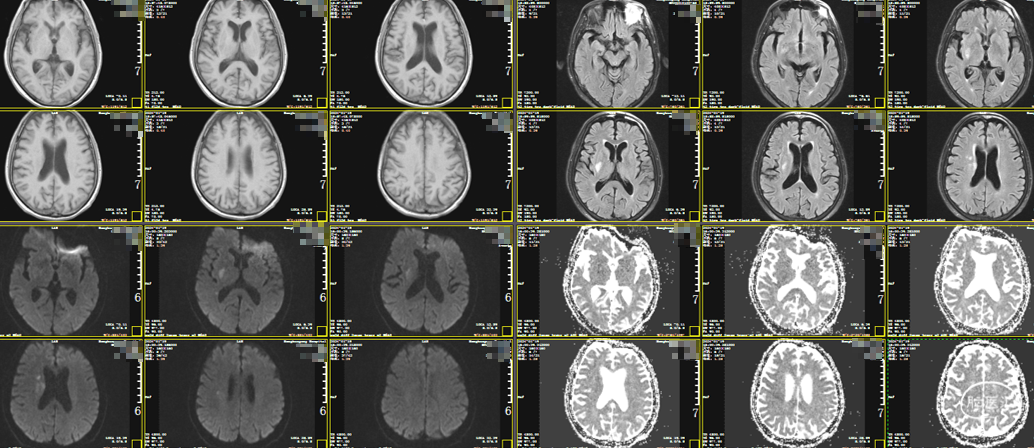

头颅MRI:右侧岛叶、基底节区、放射冠散在急性脑梗死。

头颅MRA:右侧颈内动脉闭塞。

术后1周MRI